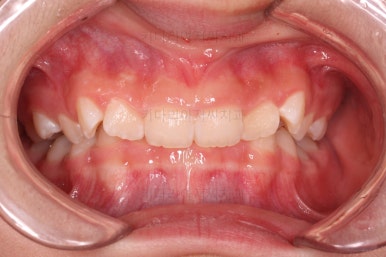

초진 시 입안의 모습입니다.

앞니가 안으로 굽어 들어간 양상인데요. 흔히 "옥니"라고 표현합니다.(뻐드렁니의 반대개념)

오른쪽 상단 사진을 보시면 어금니의 높이와 앞니의 높이가 차이가 많이 납니다.

앞니가 솟구쳐 있는 양상인데요.

그 이유 때문에 어금니로 다물었을 때의 위아래 앞니가 많이 겹쳐서 아래 앞니가 아예 보이지 않는 상황이었어요.

이를 "과개교합"이라고 표현합니다.